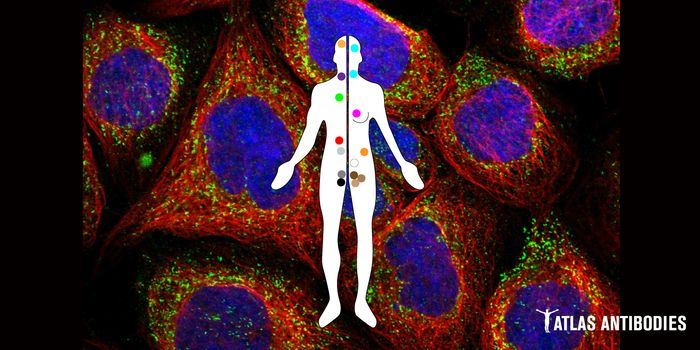

MAY 06, 2024ImmunologyPublished by Bindi M. Doshi, PhD In the realm of immunodiagnostics, antibodies have long been invaluable tools, e ...